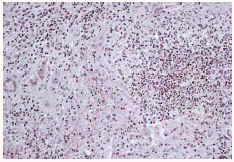

Se realizó biopsia de piel y cultivo de la misma en medios para bacterias, micobacterias y hongos. El estudio anatomopatológico mostró un patrón granulomatoso con células epiteliodes, células gigantes de Langhans, necrosis y microabscesos dispersos con neutrófilos (Fig. 2). En la tinción de Ziehl-Neelsen de la biopsia se observaron numerosos bacilos ácido-alcohol resistentes. En el cultivo de la biopsia cutánea se desarrollaron colonias de bacilos ácido-alcohol resistentes en 5 días. La identificación de esta micobacteria como M. chelonae se realizó mediante técnicas genéticas de microbiología molecular, concretamente con PRA (PCR-restriction analysis enzimes patterns). En el antibiograma realizado mostraron sensibilidad claritromicina, eritromicina, tobramicina, amikacina, tetraciclina y doxiclina, mientras que fueron resistentes imipenem, ciprofloxacino, ofloxacino, cefoxitina y cefotaxima. Se instauró tratamiento con claritromicina 500 mg cada 12 horas con mejoría progresiva y curación completa tras 3 meses de tratamiento.

FIG. 2.--Patrón histopatológico «dimorfo» con granulomas epiteliodes con células gigantes junto a microabscesos de polinucleares.

La histopatología muestra varios patrones de presentación como granulomas tuberculoides, abscesos, paniculitis, inflamación crónica inespecífica, infiltrados difusos de histiocitos, granulomas desnudos o sarcoideos y nódulos reumatoides-like (18). La observación del llamado patrón bifásico o dimórfico consistente en la presencia de microabscesos de polinucleares en la dermis y tejido subcutáneo junto a granulomas epiteliodes con o sin necrosis parece ser el patrón histopatológico más frecuente en las infecciones por micobacterias atípicas como ha sido en nuestro caso (19). La presencia de granulomas puede estar en relación con la edad de la lesión (más frecuentes en lesiones tardías) y el estado inmune del paciente (más frecuente en inmunocompetentes). Con la tinción de Ziehl-Neelsen se pueden encontrar en ocasiones bacilos ácido alcohol resistentes, cuyo número suele ser mayor en pacientes inmunodeprimidos (19).